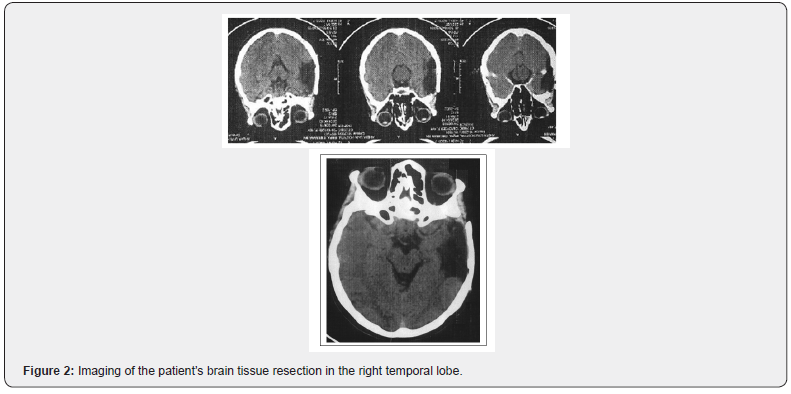

In particular, particular deficiencies were found in vigilance (ability to respond), as well as in vigilance (general receptivity to stimuli and readiness for response). Deficits in the dimensions of both immediate and long-term memory were characteristic. The patient showed that she maintains at normal levels the ability to perform daily activities as well as to assess / control reality (Figures 1 & 2).

According to the results of the tests at the time, the patient showed a characteristic cognitive dysfunction with deficits in the ability of intermittent attention, coding and information processing speed, learning, functional (working) memory and executive function. In particular, memory deficits occurred in tests requiring free recall, interpolation, and working memory, while reduced attention deficit was found to be directly related to difficulty concentrating on a task. Delusional persecution ideas as well as depressive symptoms were reported by the patient. The overall deficit score obtained from the examination is related to her medical history according to which at the age of 31 she suffered TBI in a car accident and at the age of 35 she underwent a craniotomy to remove subdural hematoma in the right temporal lobe associated with seizures. (post-traumatic epilepsy).

The patient M.K. 49 years old, from Albania, she lives with her estranged husband. Reported onset of symptoms from the age of 31 (2001) when he had suffered a craniocerebral injury following a car accident (subdural hematoma of the temporal lobe, followed by craniotomy after four years at the age of 35) [12,13]. After the injury, “E” seizures, mixed anxiety and depression, outbursts of anger and impulsive behavior are reported. Worsening of symptoms has been reported for two years (she voluntarily discontinued her medication) with delusional ideas of persecution and counseling, irritability, aggression, auditory and visual hallucinations, lack of anesthesia and non-compliance with medication. In October 2018, she additionally presented behavioral disorganization (she set fire to the clothes of her husband). Its overall functionality after the accident is reported to be very low. No developmental disorders are reported from her personal memory. She has two adult children. No abuses are reported and she had two hospitalizations. The first was unintentional (March 2017) at the Psychiatric Hospital of Leros- Greece, lasting about two weeks due to behavioral disorganization and delusional ideas of persecution and counseling on the ground of post-traumatic epilepsy. The second hospitalization was voluntary at the University Psychiatric Clinic of AUTh, Greece, lasting one week in October 2018, with a diagnosis at the time of discharge: a) F06.2- organic (schizophrenic) delusional disorder, b) G98 - other disorders of the nervous system, not classified elsewhere. The medication he was receiving was as follows: 1) Zypadhera 405mg i.m. once a month, 2) tb Aloperidin 10mg ½- 1 / 2-1, 3) tb Akineton 2mg 1-0-1, 4) tb Stedon 10mg 1-1-1,5) tb Trileptal 300mg 1-1-1, 6) tb Filicine 5mg 0-1-0. Her family psychiatric history as well as other medical history are freely mentioned [14].